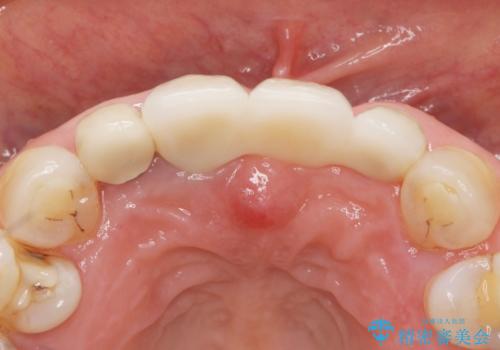

抜歯後歯肉の治癒を十分に待ったのち、ブリッジによる補綴治療を行いました。

- ¥1,010,000 (仮歯×9本、ファイバーコア×1本、ジルコニアクラウン スタンダード×9本)費用は治療当時の料金となります

ジルコニアクラウン スタンダード